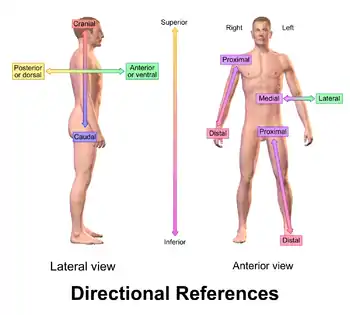

Superior and inferior

Superior (from Latin super 'above') describes what is above something[20] and inferior (from Latin inferus 'below') describes what is below it.[21] For example, in the anatomical position, the most superior part of the human body is the head and the most inferior is the feet. As a second example, in humans, the neck is superior to the chest but inferior to the head.

Anterior and posterior

Anterior (from Latin ante 'before') describes what is in front,[22] and posterior (from Latin post 'after') describes what is to the back of something.[23] For example, for a dog the nose is anterior to the eyes and the tail is considered the most posterior part; for many fish the gill openings are posterior to the eyes but anterior to the tail.

Medial and lateral

These terms describe how close something is to the midline, or the medial plane.[2] Lateral (from Latin lateralis 'to the side') describes something to the sides of an animal, as in "left lateral" and "right lateral". Medial (from Latin medius 'middle') describes structures close to the midline,[2] or closer to the midline than another structure. For example, in a human, the arms are lateral to the torso. The genitals are medial to the legs. Temporal has a similar meaning to lateral but is restricted to the head.

Proximal and distal

The terms proximal (from Latin proximus 'nearest') and distal (from Latin distare 'to stand away from') are used to describe parts of a feature that are close to or distant from the main mass of the body, respectively.[29] Thus the upper arm in humans is proximal and the hand is distal.

"Proximal and distal" are frequently used when describing appendages, such as fins, tentacles, and limbs. Although the direction indicated by "proximal" and "distal" is always respectively towards or away from the point of attachment, a given structure can be either proximal or distal in relation to another point of reference. Thus the elbow is distal to a wound on the upper arm, but proximal to a wound on the lower arm.[30]

Dorsal and ventral

These two terms, used in anatomy and embryology, describe something at the back (dorsal) or front/belly (ventral) of an organism.[2]

The dorsal (from Latin dorsum 'back') surface of an organism refers to the back, or upper side, of an organism. If talking about the skull, the dorsal side is the top.[38]

The ventral (from Latin venter 'belly') surface refers to the front, or lower side, of an organism.[38]

Rostral, cranial, and caudal

Specific terms exist to describe how close or far something is to the head or tail of an animal. To describe how close to the head of an animal something is, three distinct terms are used:

- Rostral (from Latin rostrum 'beak, nose') describes something situated toward the oral or nasal region, or in the case of the brain, toward the tip of the frontal lobe.[39]

- Cranial (from Greek κρανίον 'skull') or cephalic (from Greek κεφαλή 'head') describes how close something is to the head of an organism.[40]

- Caudal (from Latin cauda 'tail') describes how close something is to the trailing end of an organism.[41]